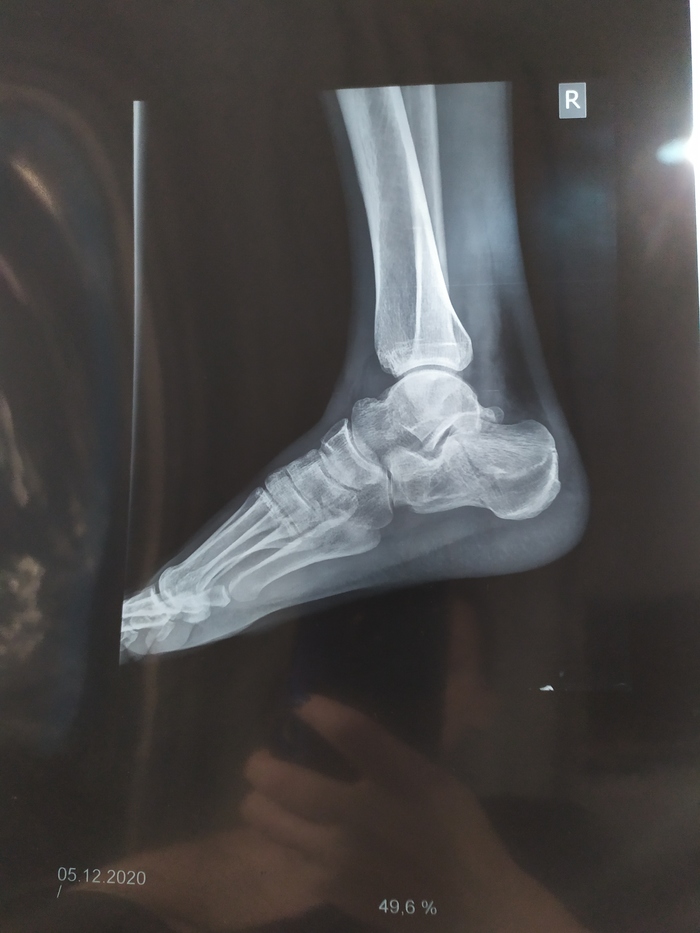

Примерочный вариант.

Итоговый вариант с внутренними мягкими "стаканами" в ногах, которые в точности повторяют форму мышц.